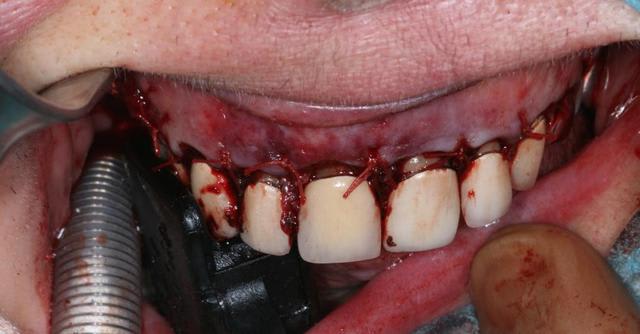

Ce matin j'ai opéré une patiente pour un bon kyste maxillaire d'origine dentaire très certainement et quelques petits sur d'autres dents.

Dans un premier temps j'ai disséqué le kyste qui a détruit le plancher des fosses nasales et le mur palatin.

Dans un second temps j'ai fait des préparations à rétro sur les dents causales (11-21-22-14). Puis j'ai réalisé un collage à rétro car les tenons atteignaient les apex.

Enfin j'ai isolé par des membranes Biogide et comblé avec du bétaTCP.

Techniquement, je ne pense pas que tu ai fais de "vraies" préparations a retro... ;-) Et de toute façon, l'intérêt d'une préparation a retro...c'est d'obturer a retro. Tu as bien fais de faire un collage dans ce cas précis, mais je trouve le site très hémorragique. As-tu utilisé un anesthésique local pour la vasoconstriction ?

Dernière remarque : l'incision me semble intrasulculaire (ce qui est préjudicable à l'esthétique des prothèses. Et enfin, d'un point de vue perso, lorsque je compare les cicatrices que j'obtiens avec du 6-0 et celles des stomatos du coin qui utilisent du 3-0 il n'y a pas photo...je pense qu'il y a vraiment un lien entre les deux. Peut être aussi dans le fait qu'ils ont tendance à "serrer à mort" leurs points de sutures créant une ischémie à ce niveau, propice à une cicatrice plus disgracieuse.